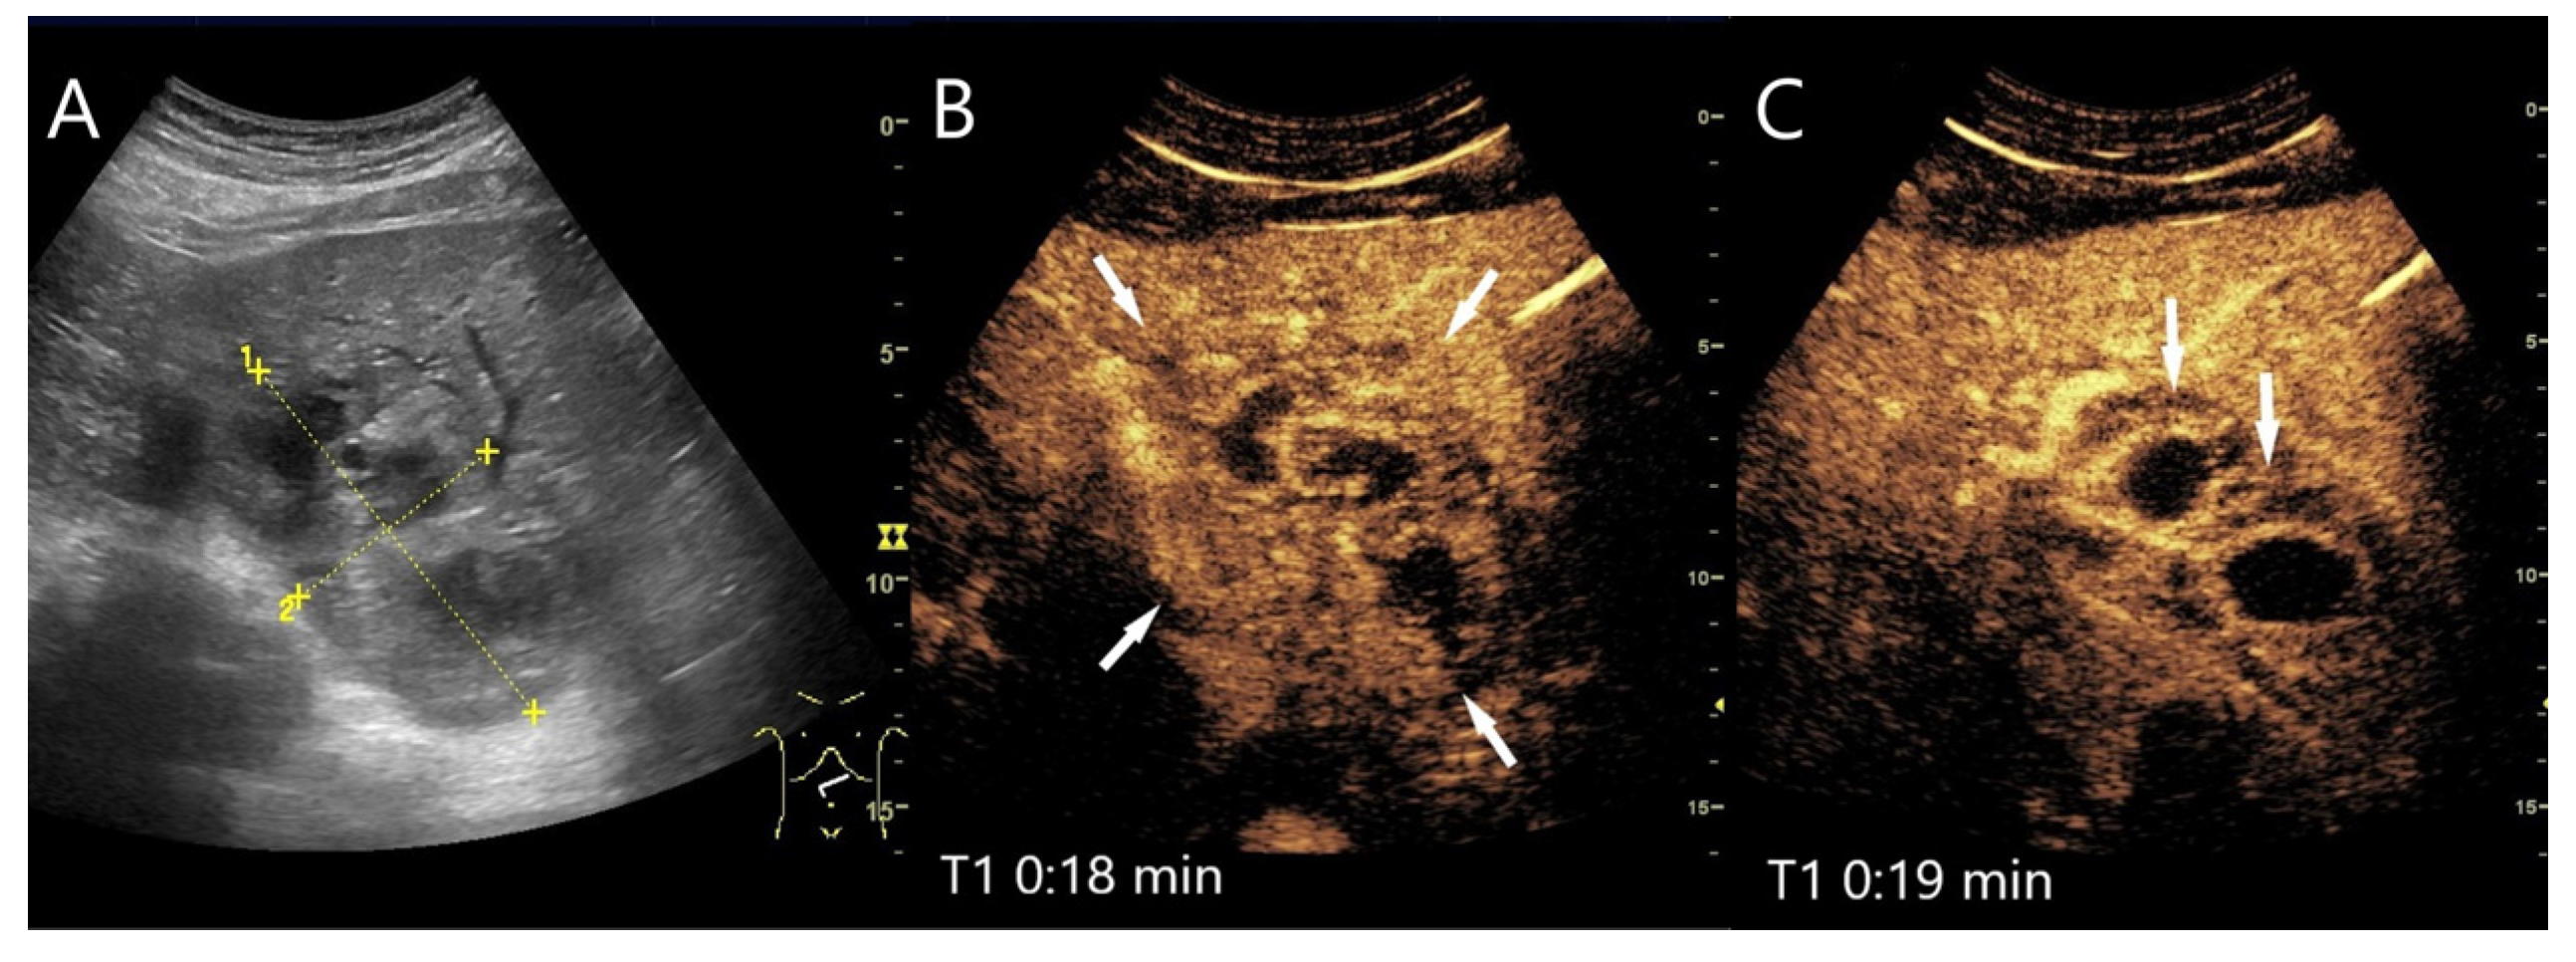

| Abscesses | Hypo-/anechoic. | Hyperenhancement in phlegmonous stage, transient hyperenhancement in surrounding parenchyma. Non-enhancement of necrotic parts. Honeycomb sign. | Early washout. | Formation of thromboses of the small hepatic and portal veins, as well as pylephlebitis of the small portalvenous vessels. |